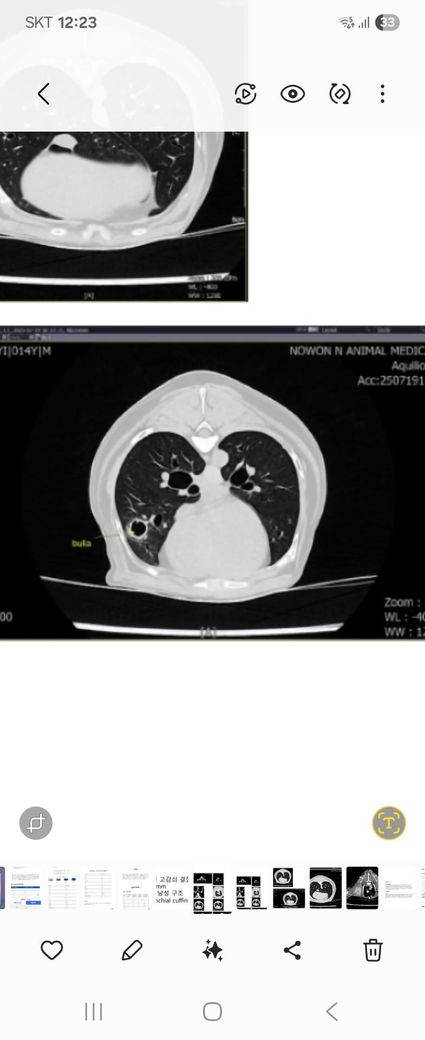

CT상 보이는건 수포가 아니라 bulla입니다. 수포는 물이찬것이고, bulla는 공기가 찬 주머니라 완전히 의미가 다릅니다.

매우 작은 공기주머니로 구성되어 있는 폐실질 내부에 공기가 차있는 bulla가 들어 있으면 엑스레이상에서는 상당히 커기지 전까지 관찰되지 않는게 정상입니다. 즉, CT검사의 민감도가 높아서 잘 보이는것일 뿐 방사선에서 보이지 않는건 일반적인 현상입니다.

다만 시간경과에 따라 크기가 점차 커지거나, 내부에 농이 차오르면 문제가 되기도 하니 주기적인 방사선 검사를 통해 변화 양상 모니터링을 해보는게 추천됩니다.

이론적으로 갑자기 bulla가 발생할 수는 있지만 대부분 오래전부터 서서히 진행되다 우연히 발견된 경우가 대부분입니다.